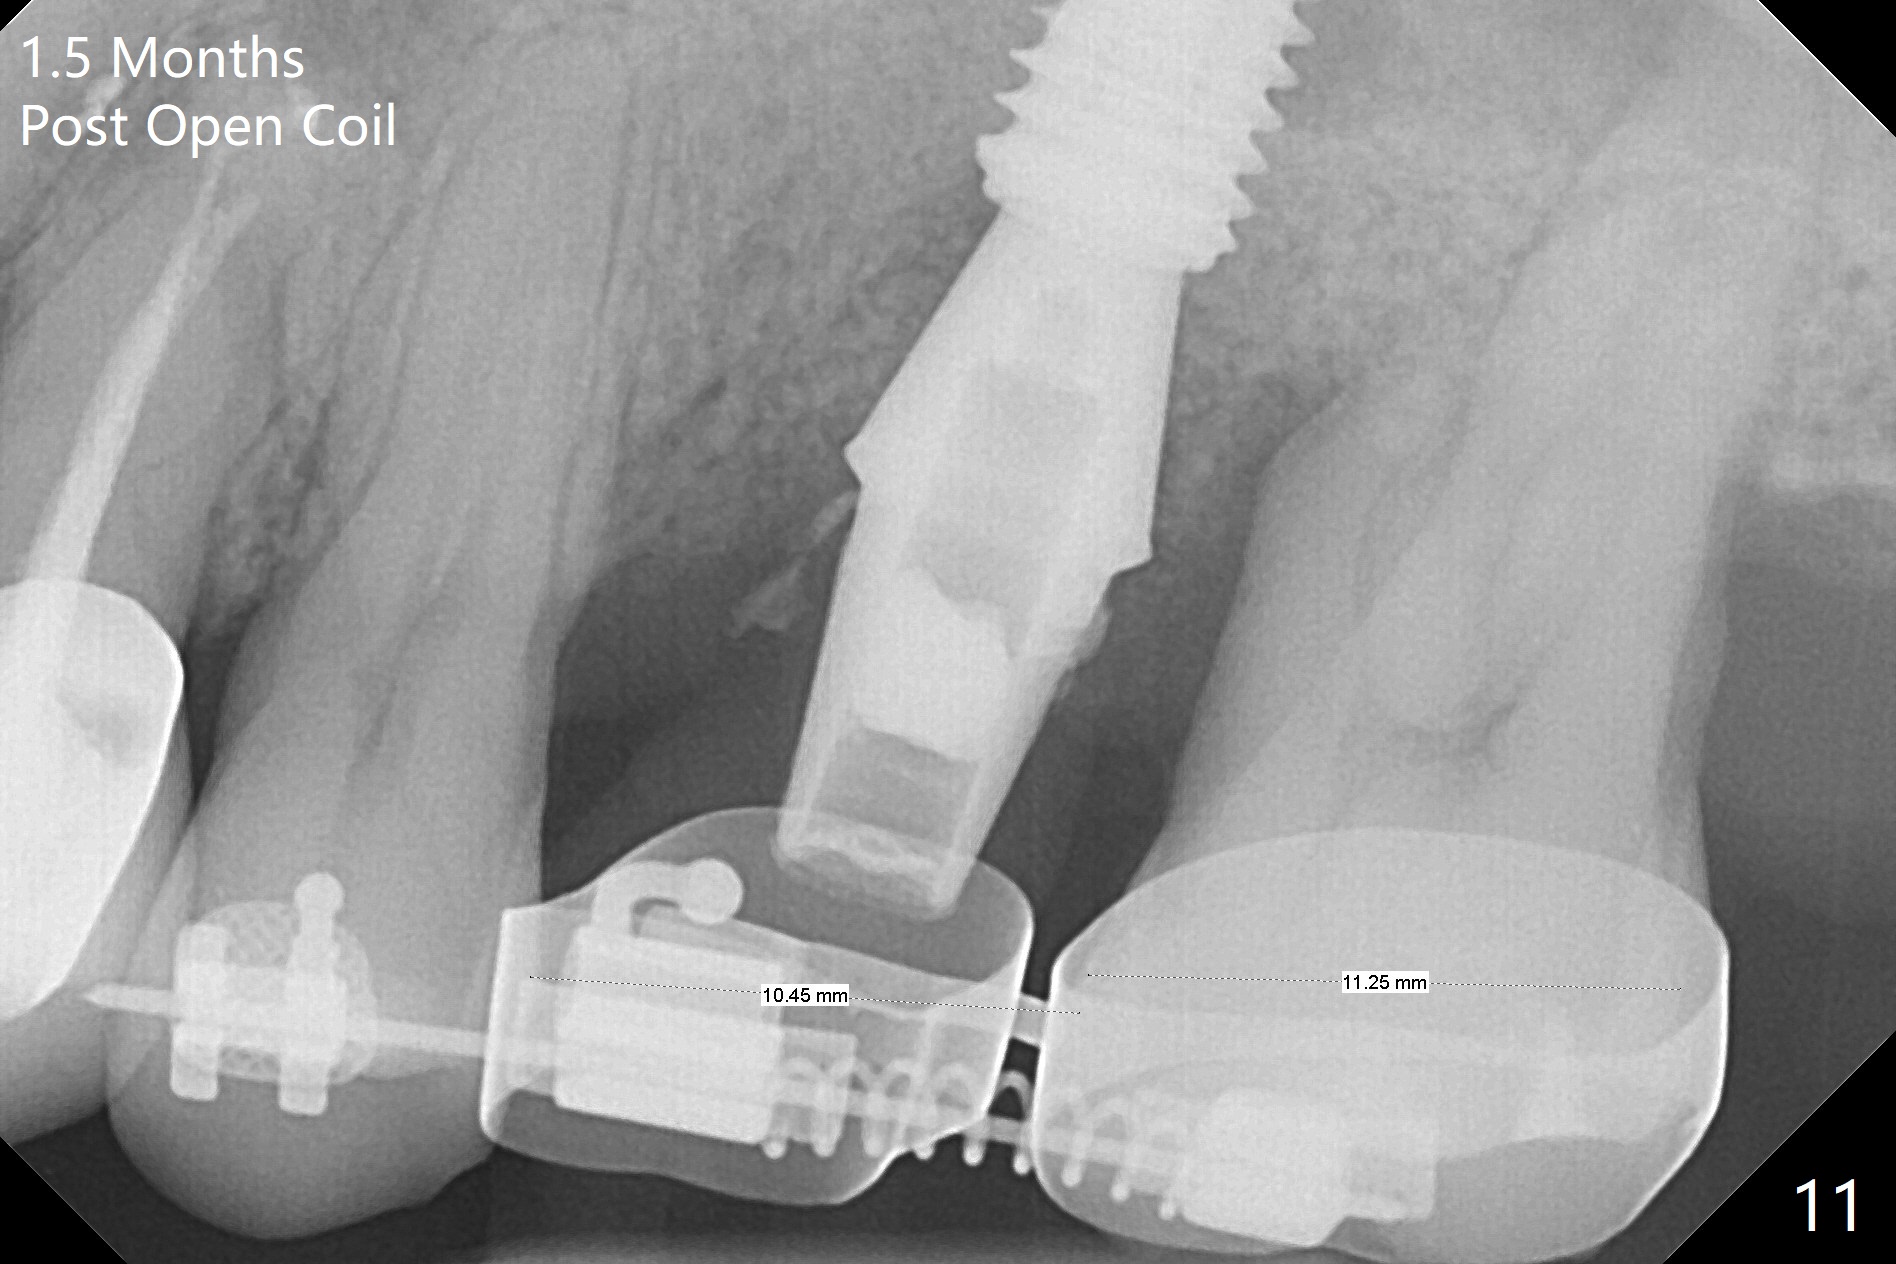

Six months post 2nd placement at #14, the 5x11 mm IBS implant is unstable. The patient smokes a cigarette a day.  After implant removal, the palatal wall of the osteotomy is intact, although low.  With removal of minimal granulation tissue, a 5x10 mm IS dummy implant is placed with stability and slightly subgingival palatal (Fig.1,2).  A 5x8.5 mm definitive implant is placed with ~ 40 Ncm and 3-4 mm subgingival palatal (Fig.3,4).  A 5.7x5.5(5) mm abutment is placed to hold periodontal dressing in place.  If the implant fails again, bone graft should be placed.  The abutment and implant are stable 4.5 months postop (Fig.5); a provisional is fabricated for progressive loading.  The provisional at #14 is narrow mesiodistally, while the tooth #15 is mesially tilted and shifted because of chronic periodontitis and 1 year 4 months of edentulism (Fig.6*).  Limited orthodontics is necessary prior to final restoration.  The 1st step is to raise the occlusion with #14 temporary reline (Fig.7 *); the tooth #15 is distalized initially with a separator, which is inefficient.  It appears that brackets and bands should be placed for distalization.  A month post banding, open coil spring is placed between #14 and 15; with occlusal composite on the opposing tooth (#19) (Fig.8), the tooth #15 is distalized instantly probably related to its periodontal condition (Fig.9 mirror view).  The tooth #15 is further distalized 2 weeks post open coil spring placement (Fig.10).  To act an anchorage, the abutment needs to be torqued with wrench (25-30 Ncm) and the provisional has to be permanently cemented.  The distalization appears to be ~ 1 mm shy 1.5 months post open coil (Fig.11).